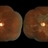

- degeneration paravenous

Zeiss / VisuCam-500 - Angulation of field photo of 45 Degrees, flash 11.

- Female patient, 32-years-old, Asian, appeared at the clinic with a history of glaucoma. 20/20 Visual acuity in both eyes. Examination of color photography, pigmentary changes were observed following the vascular arcades only in the left eye. Suggestive of paravenous degeneration.